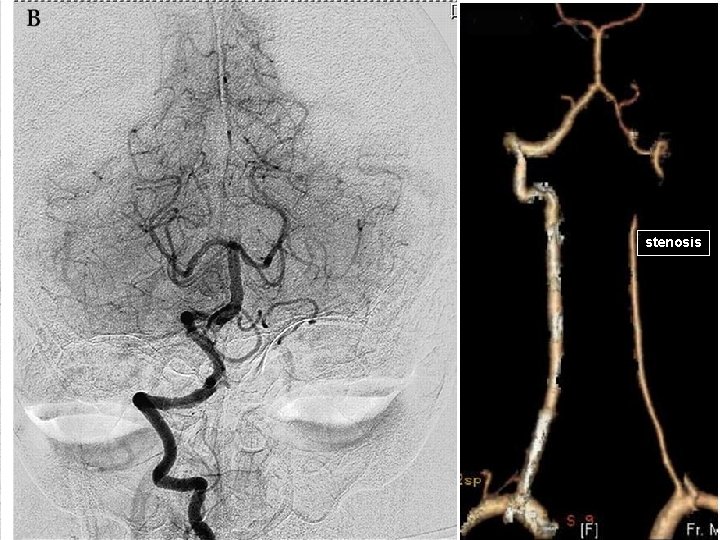

Clinical division of ACI Bouthillier‘s classification: C 1 = cervical segment (the bulb is indicated by stippling, and the ascending segment by horizontal lines) C 2 = petrous segment C 3 = lacerum segment C 4 = cavernous segment C 5 = clinoidal segment C 6 = ophthalmic segment C 7 = communicating segment Reprinted with permission from Osborn AG: Diagnostic Cerebral Angiography, ed 2, Lippincott Williams & Wilkins, Philadelphia, 1999.

stenosis

Aneurysm of ACI